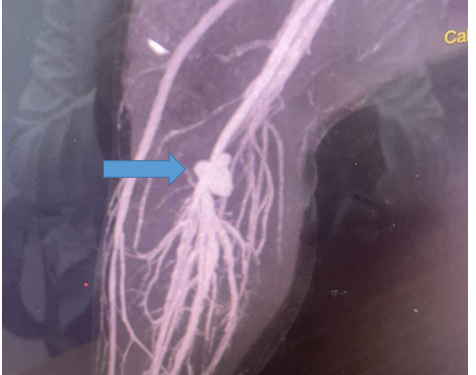

Kết quả chụp CT mạch máu cản quang cho thấy bệnh nhi bị hẹp đoạn cuối động mạch khoeo và tắc đoạn cuối tĩnh mạch kheo tại vị trí túi phình.

Bác sĩ Tiến lý giải, vết thương do kéo gây rách da, rách cơ và động mạch, đứt tĩnh mạch. Máu từ động mạch rỉ ra, trào ra mô xung quanh tạo thành cục máu đông, thông giữa động và tĩnh mạch, tạo thành túi phình.

“Túi phình nguy hiểm vì gây cản trở khi máu theo động mạch đi xuống nuôi chi. Ngược lại, máu theo tĩnh mạch đi lên cũng khó khăn. Do đó, chân bị thiếu tưới máu và sưng rất nhiều. Nếu không can thiệp kịp thời, trẻ có thể phải đoạn chi”, bác sĩ nói.